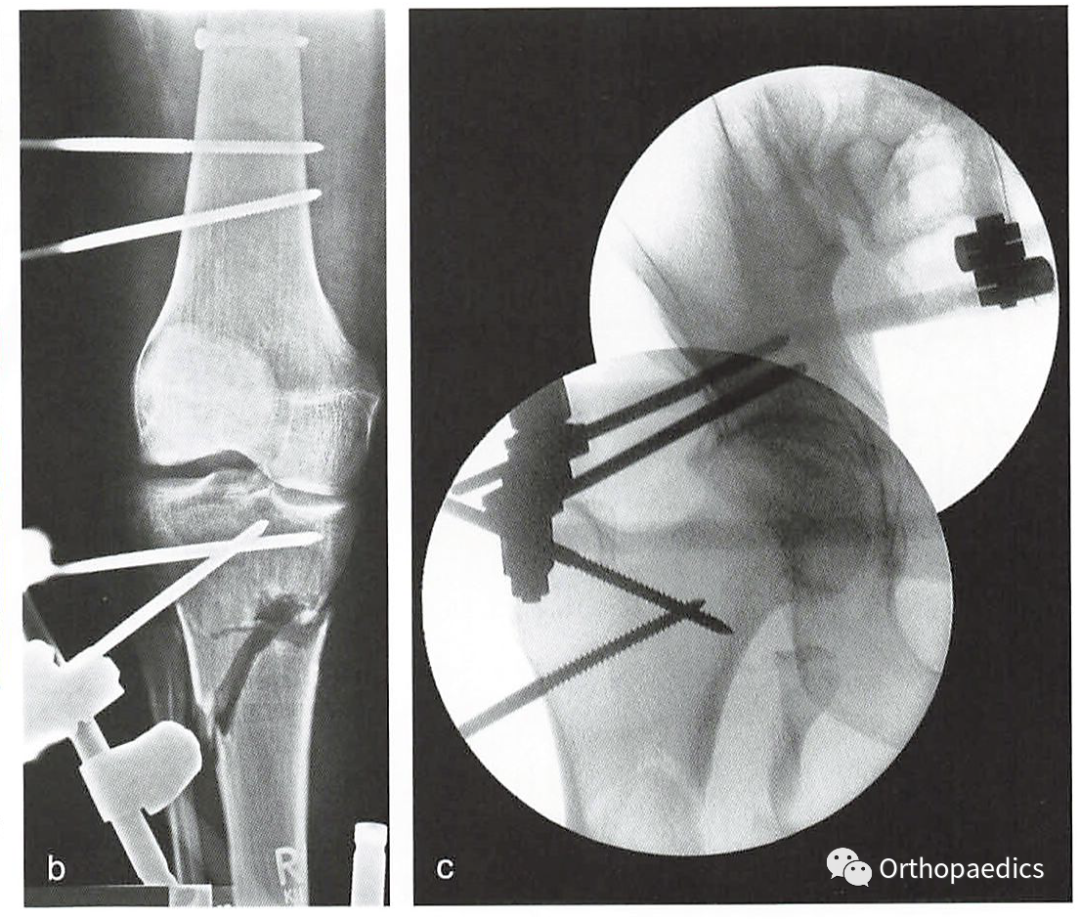

▲组合式外固定架演示。a 胫骨。b 股骨。c 跨膝关节。